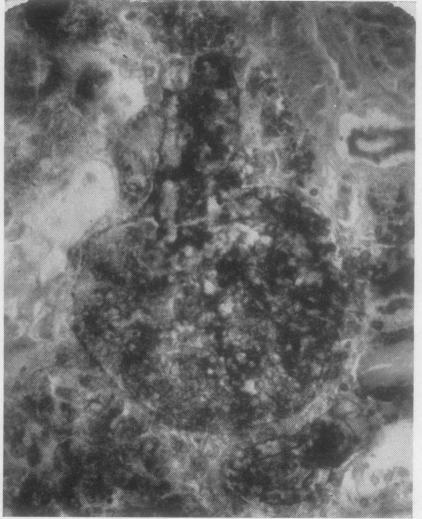

Clinico-pathological details are given of a patient who survived bilateral renal cortical necrosis for 44 days as a result of treatment by haemodialysis. Cortical calcification was demonstrable radiologically in life and at necropsy. The literature pertaining to renal ischaemic damage and calcification is reviewed. Conclusions are drawn as to the mechanism that produces renal cortical calcification in the light of previous experimental work and the study of the present case. It is suggested that the widespread use of haemodialysis in treatment is likely to result in the detection of an increasing number of such cases.

本文给出了一名患者的临床病理细节,该患者因接受血液透析治疗,双侧肾皮质坏死存活了44天。生前及尸检时影像学检查均显示皮质钙化。本文回顾了有关肾缺血性损伤和钙化的文献。根据以往的实验研究及本病例的研究,得出了产生肾皮质钙化的机制。本文认为,血液透析在治疗中的广泛应用可能会导致越来越多此类病例被发现。